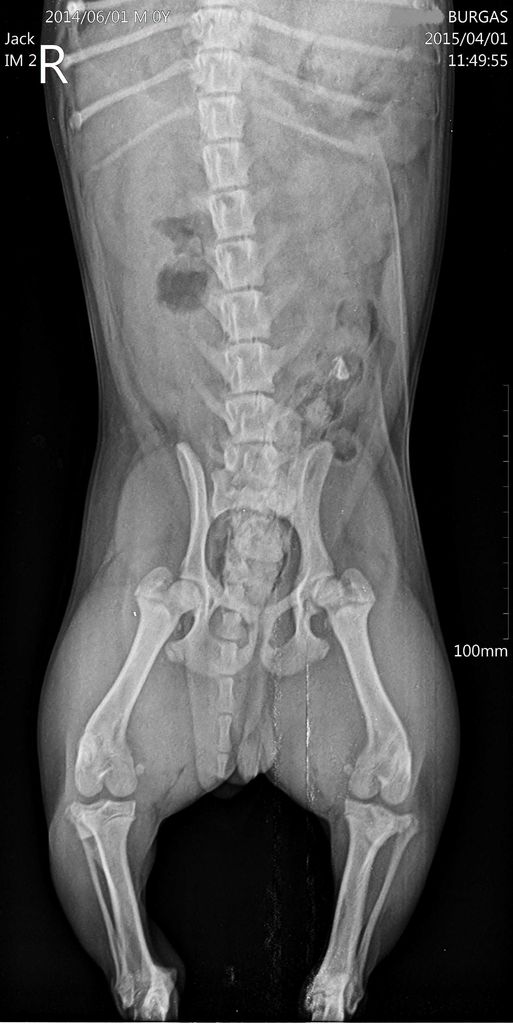

Счупено дясно краче

Добро утро!Искам да попитам на тези снимки които изпращам вижда ли се отчупване на костица от колянната става или някакво счупване въобще?! Кученцето е на 5 месеца,

куца от 3 дни, малко стъпва на крачето!